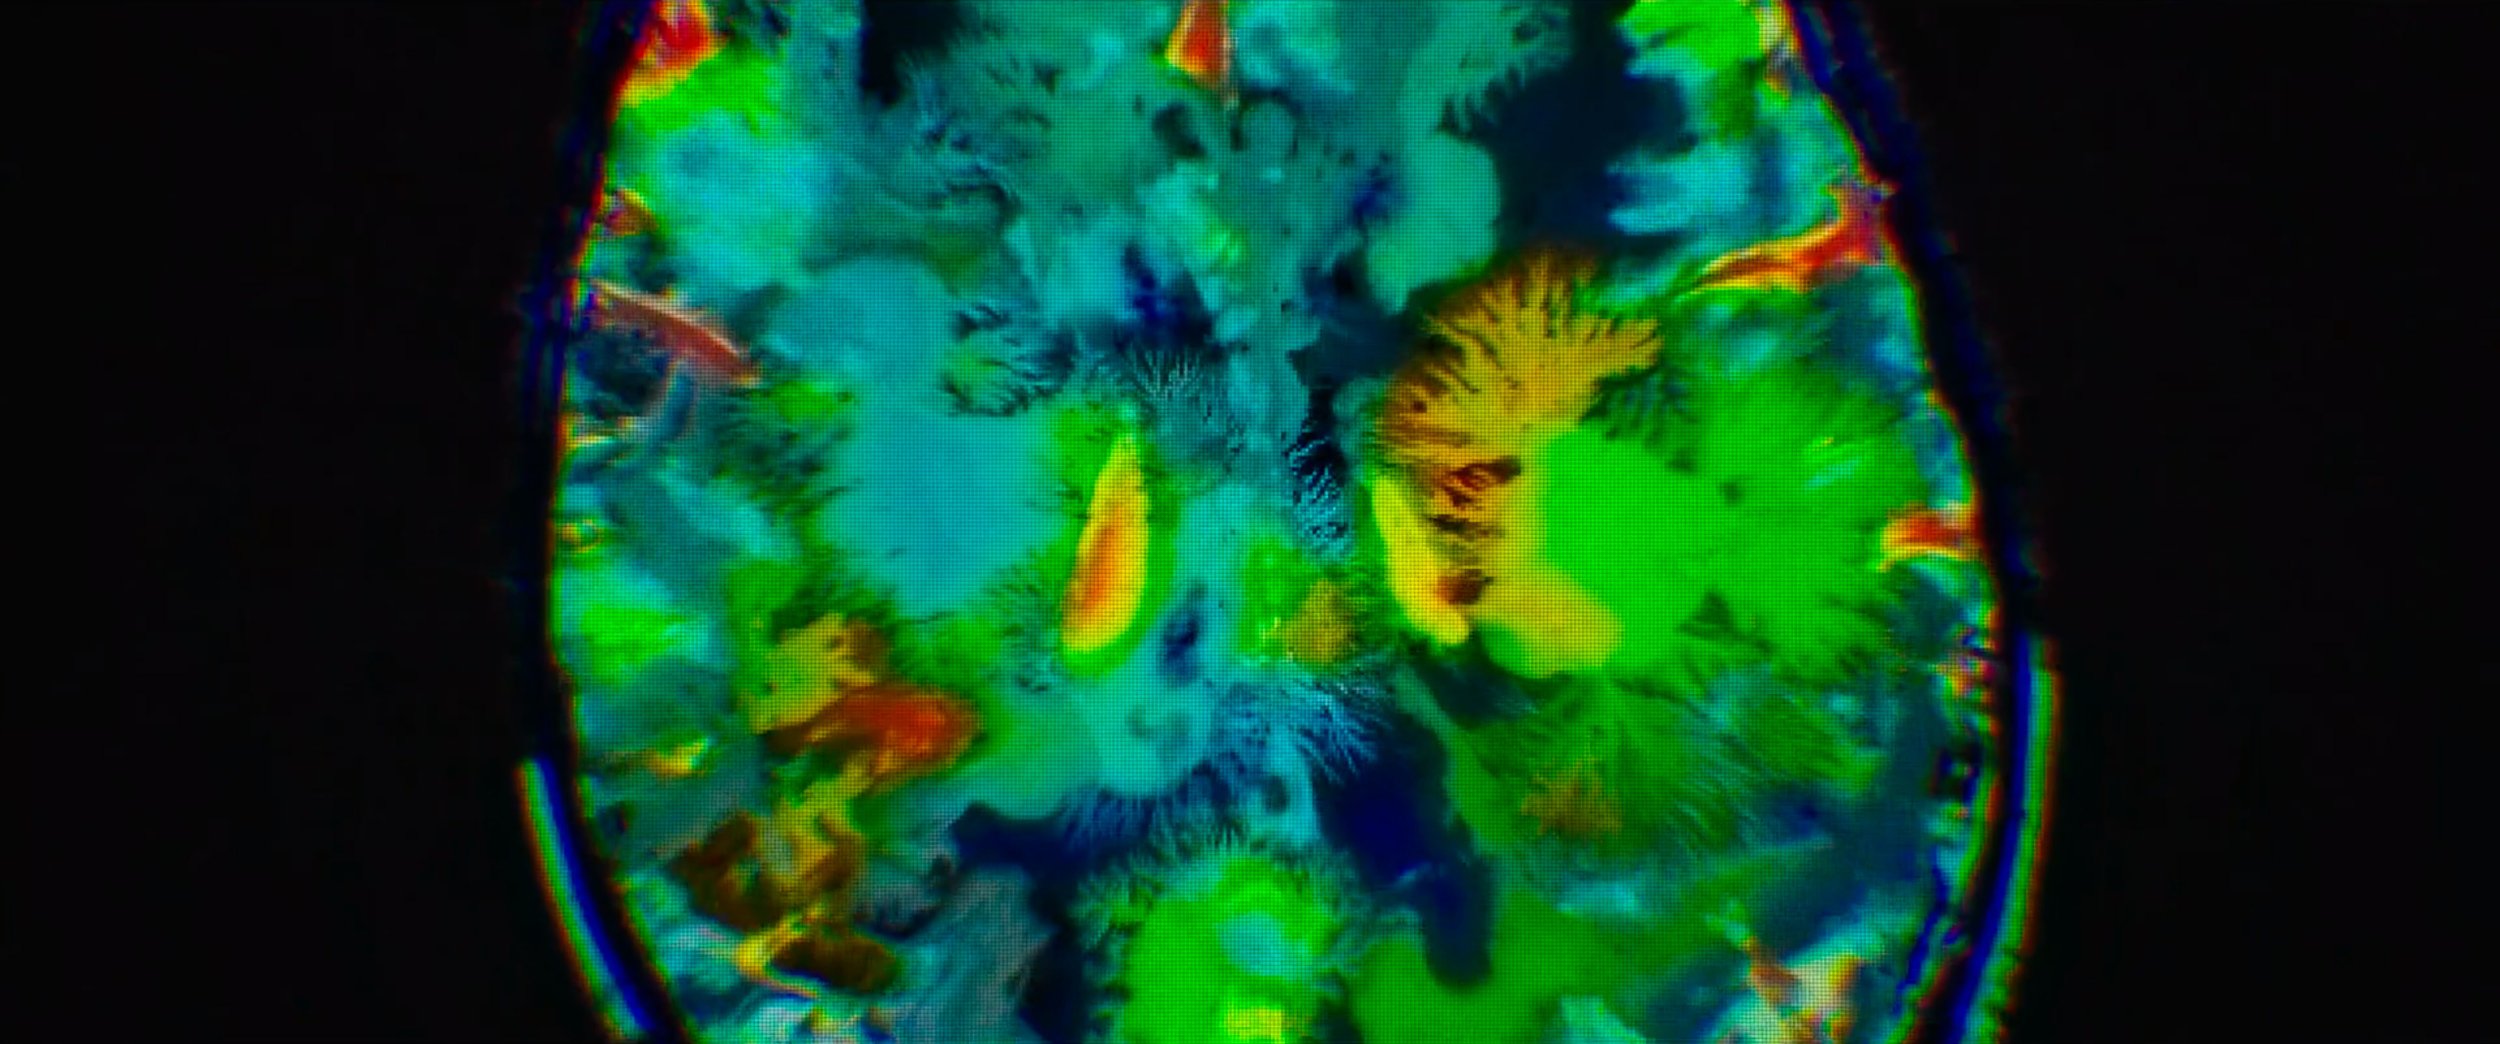

FIVE DAYS AT MEMORIAL

MAIN TITLE SEQUENCE

Role: Edit, Type Animation, Motion Design, & Compositing

Five Days at Memorial is an American disaster medical drama television miniseries based on the 2013 book of the same name. The series depicts the extreme difficulties a New Orleans hospital endures after Hurricane Katrina makes landfall on the city. The miniseries premiered on August 12, 2022, on Apple TV+.

Working again with Me & The Bootmaker and with videographer Roman Hill, I was brought in to handle compositing, edit, typography animation, and overall motion design.